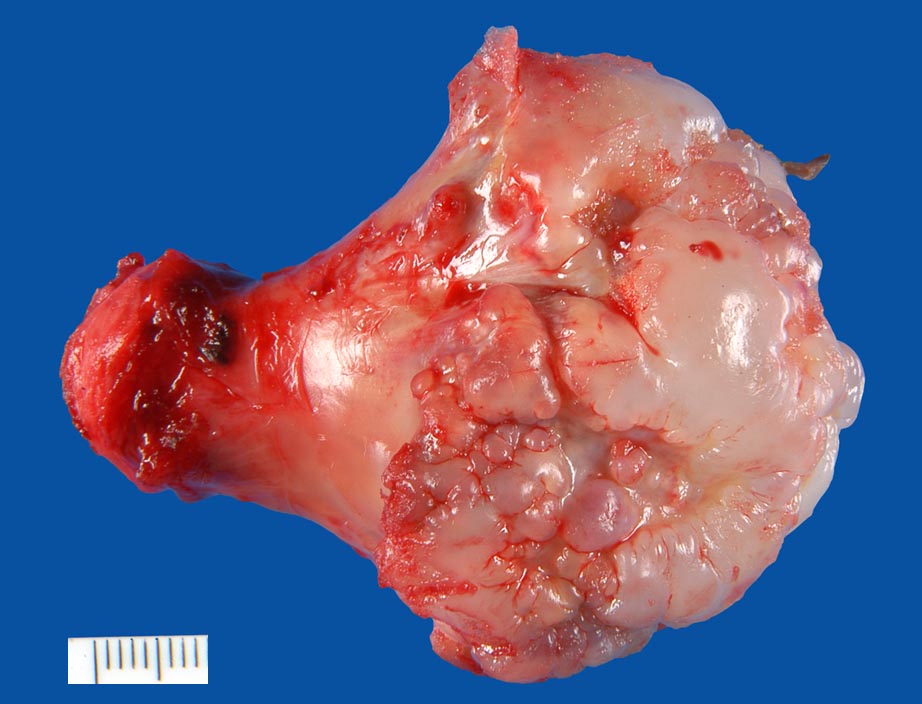

Osteochondrome sind breitbasig dem Knochen aufsitzende oder gestielte knöcherne Tumoren, die von einer 1-6mm dicken Kappe aus hyalinem Knorpel bedeckt werden. Zwischen Knorpel und Knochen liegt eine Zone enchondraler Ossifikation, die der normalen Wachstumsfuge ähnelt und den Ausgangspunkt für die Grössenzunahme des Tumors bei noch nicht abgeschlossenem Skelettwachstum darstellt. Der hyaline Knorpel wirkt etwas unorganisiert und ist bedeckt von einer dünnen Schicht Perichondrium.

Osteochondrome (Synonym: kartilaginäre Exostosen) sind nach den nicht-ossifizierenden Knochenfibromen (NOF) die häufigsten gutartigen Knochentumoren. Betroffen sind meist Patienten in den ersten zwei Lebensdekaden.

Meistens sind Osteochondrome asymptomatisch und fallen als Zufallsbefund im Röntgenbild oder als schmerzlose Knochenverdickung auf. Schmerzen können durch Traumatisierung oder Druck auf Muskeln, Sehnen oder Gefäss-Nervenbündel entstehen.

Im konventionellen Röntgenbild lassen sich gestielte und breitbasige Osteochondrome unterscheiden, wobei letztgenannte Formen immer vom Gelenk weggerichtet sind. Ein wichtiges Charakteristikum ist, dass die Spongiosa des Osteochondroms mit der Spongiosa des ortsständigen Knochens in Verbindung steht und die Läsion nicht einfach nur der Kompakta aufsitzt. Die Knorpelkappe ist im konventionellen Röntgenbild (> 5033) nur angedeutet erkennbar, kann aber im CT, MRI oder im Ultraschall dargestellt und ausgemessen werden. In der Mehrzahl der sporadischen aber v.a. der hereditären Osteochondrome lassen sich biallelische Inaktivierungen des EXT1 oder EXT2 Gens nachweisen, was die neoplastische Genese der Läsionen unterstreicht.